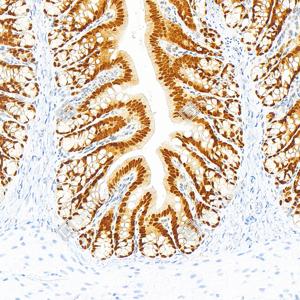

| IHC检测CDX2蛋白(货号 GB150083). 样品: 人结肠, 4%多聚甲醛 (货号G1101) 固定12-24小时. 抗原修复: Tris-EDTA抗原修复液(pH 9.0) (G1203), 100℃, 25分钟. —抗: 1: 10000稀释, 4℃ 孵育过夜. 二抗: S-vision免疫组化多聚二抗(山羊抗兔),即用型 (货号G1302), 室温孵育20分钟. |